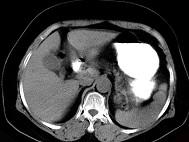

女43岁上腹不适多年,体检行CT扫描如图,最可能的诊断为 ( )A.胃癌B.胃平滑肌瘤C.胃平滑肌肉瘤D.胃淋巴瘤E.胃蛔虫团块

问题 女43岁上腹不适多年,体检行CT扫描如图,最可能的诊断为 ( )

选项 A.胃癌 B.胃平滑肌瘤 C.胃平滑肌肉瘤 D.胃淋巴瘤 E.胃蛔虫团块

答案 B